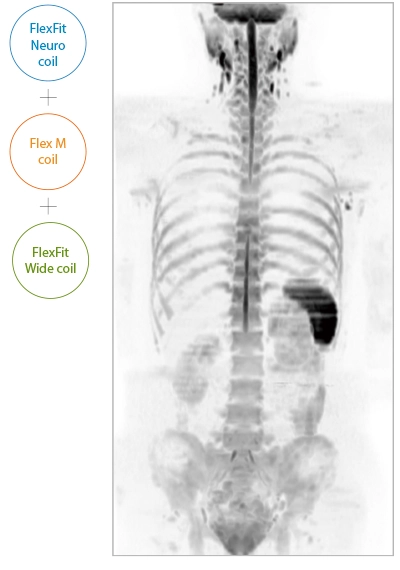

IP-RAPID x DLR Plus can be used for basic imaging such as VolumeScan, RadialScan, HalfScan, and many other imaging methods such as MultiContrastScan FatSep and DWI.

It can also be used with time-consuming scans such as Whole Body DWI and Whole Spine imaging, providing more detailed information in many areas than previously possible.